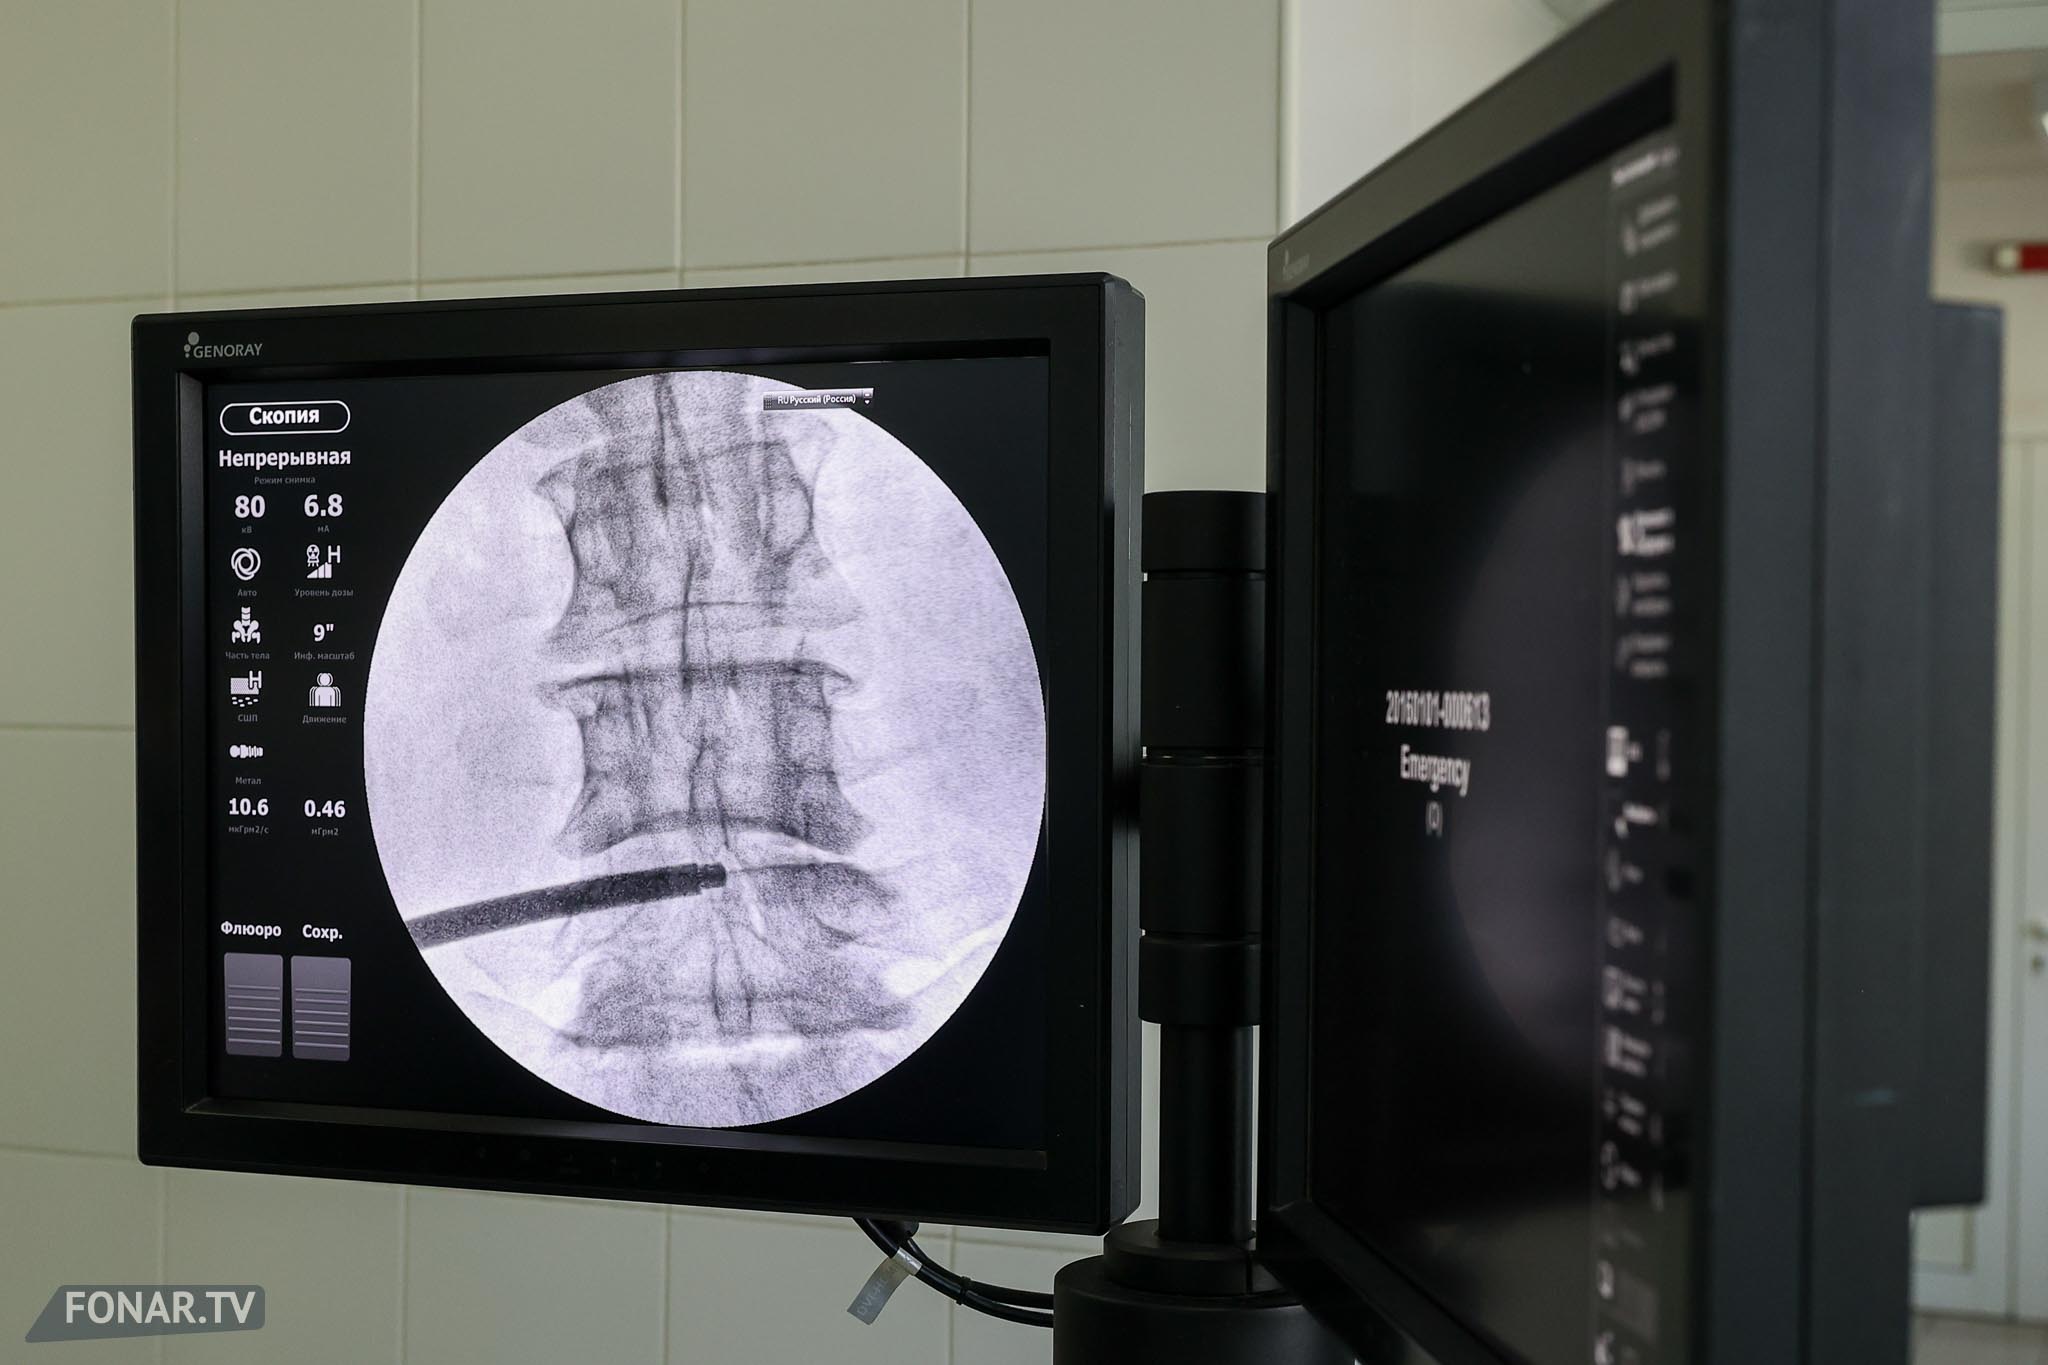

Ранним утром в четверг, 14 августа, в операционной Белгородской областной клинической больницы — тишина и свет софитов. За несколько часов врачи делают то, что ещё недавно казалось невозможным: через разрез всего в один сантиметр нейрохирурги устанавливают пациенту титановую конструкцию, которая возьмёт на себя работу повреждённого позвоночника.

Это первая в России малоинвазивная MISTPF-операция с использованием отечественной транспедикулярной системы. До сих пор такие вмешательства проводились только «открытым» способом — с большой травматизацией тканей и долгой реабилитацией. Теперь — совсем другое дело: минимальные повреждения, меньше боли, быстрее возвращение к жизни.

В фоторепортаже Антона Вергуна — кадры из операционной: точная работа рук хирургов, стерильный блеск инструментов и момент, когда титановая система занимает своё место, чтобы навсегда изменить судьбу пациента.